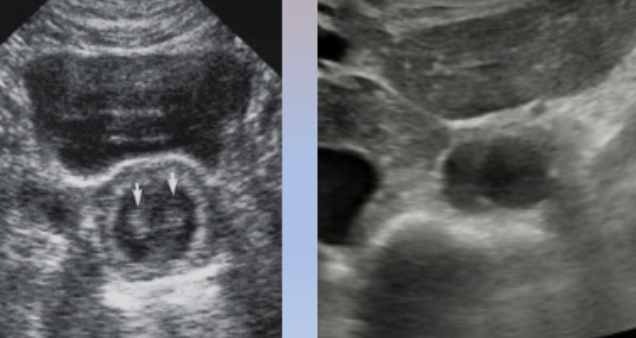

Happens quite frequently at the midline of the body, especially in the abdomen, because of the rectus abdominis muscles

This often affects the aorta in transverse, so you would just slide the transducer laterally